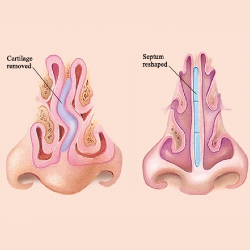

Septoplasty

Septoplasty helps to straighten your nose by reshaping the wall between your nasal passages. If you have a crooked nose due to a deviated septum, your doctor will likely recommend septoplasty.

In addition to straightening your nose, septoplasty can also relieve nasal airway blockage caused by a deviated septum.

Septorhinoplasty

A Septorhinoplasty also known in the non-medical terms as (“nose job”) is a surgical procedure that involves operating on the bones and cartilage that give your nose its shape and structure and making your septum straight.

It has a two-fold objective to improve the appearance of your nose (Rhinoplasty) and to improve how you breathe through your nose (Septoplasty).